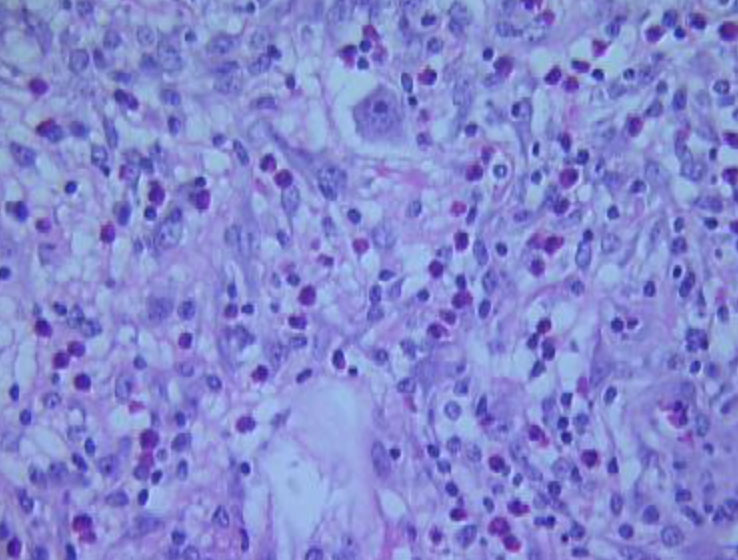

Micro: Acantholysis c lots of dyskeratosis, esp in lower epidermis

- more dyskeratosis, but less acantholysis than Familial b9 chronic pemphigus (Hailey-Hailey dz); and also do not have the red halo, but a blue or white halo around dyskeratotic nuclei

forms clefts and lacunae

- irregular upward proliferation of papillae lined by single layer of basal cells (villi) into the lacunae

- Grains and corps ronds (characteristic dyskeratotic cells)

Darier's dz

Dare to dx Darier's dz